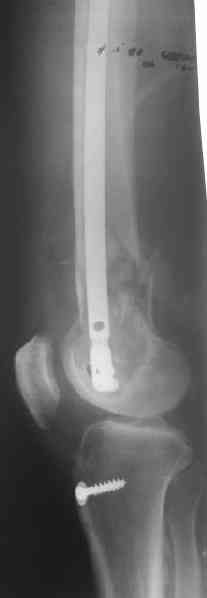

Удалили ластину без проблем. Выявилась значительная подвижность. В этих условиях сразу пропала мотивация к постепенной коррекции аппаратом. Попробовал восстановить длину, введя между отломками spreader. Отчасти удалось. Тогда защили рану, наложили спицевой дистрактор (2 спицы в дистальный отдел и 1 вверху). после этого был убран и спонгиозный винт. И сделали антгерадное штифтование, как говорится, "по принятой в

клинике методике".

Дополнительные доступы для введения гвоздя и проксимальных винтов понадобились, но они маленькие, по 1 см. Нижние винты ввели прямо между швами. Суставы дополнительно не травмировали, и даже ввели гвоздь не через f. piriformis, а через большой вертел.

Длину восстановили, возможно, даже с изьбытком, ну да динамизируем пораньше. Введенные в овальное отверстие дистальые винты имеют угловую стабильность. Снимки приложены. Заранее спасибо за критику и комментарии.